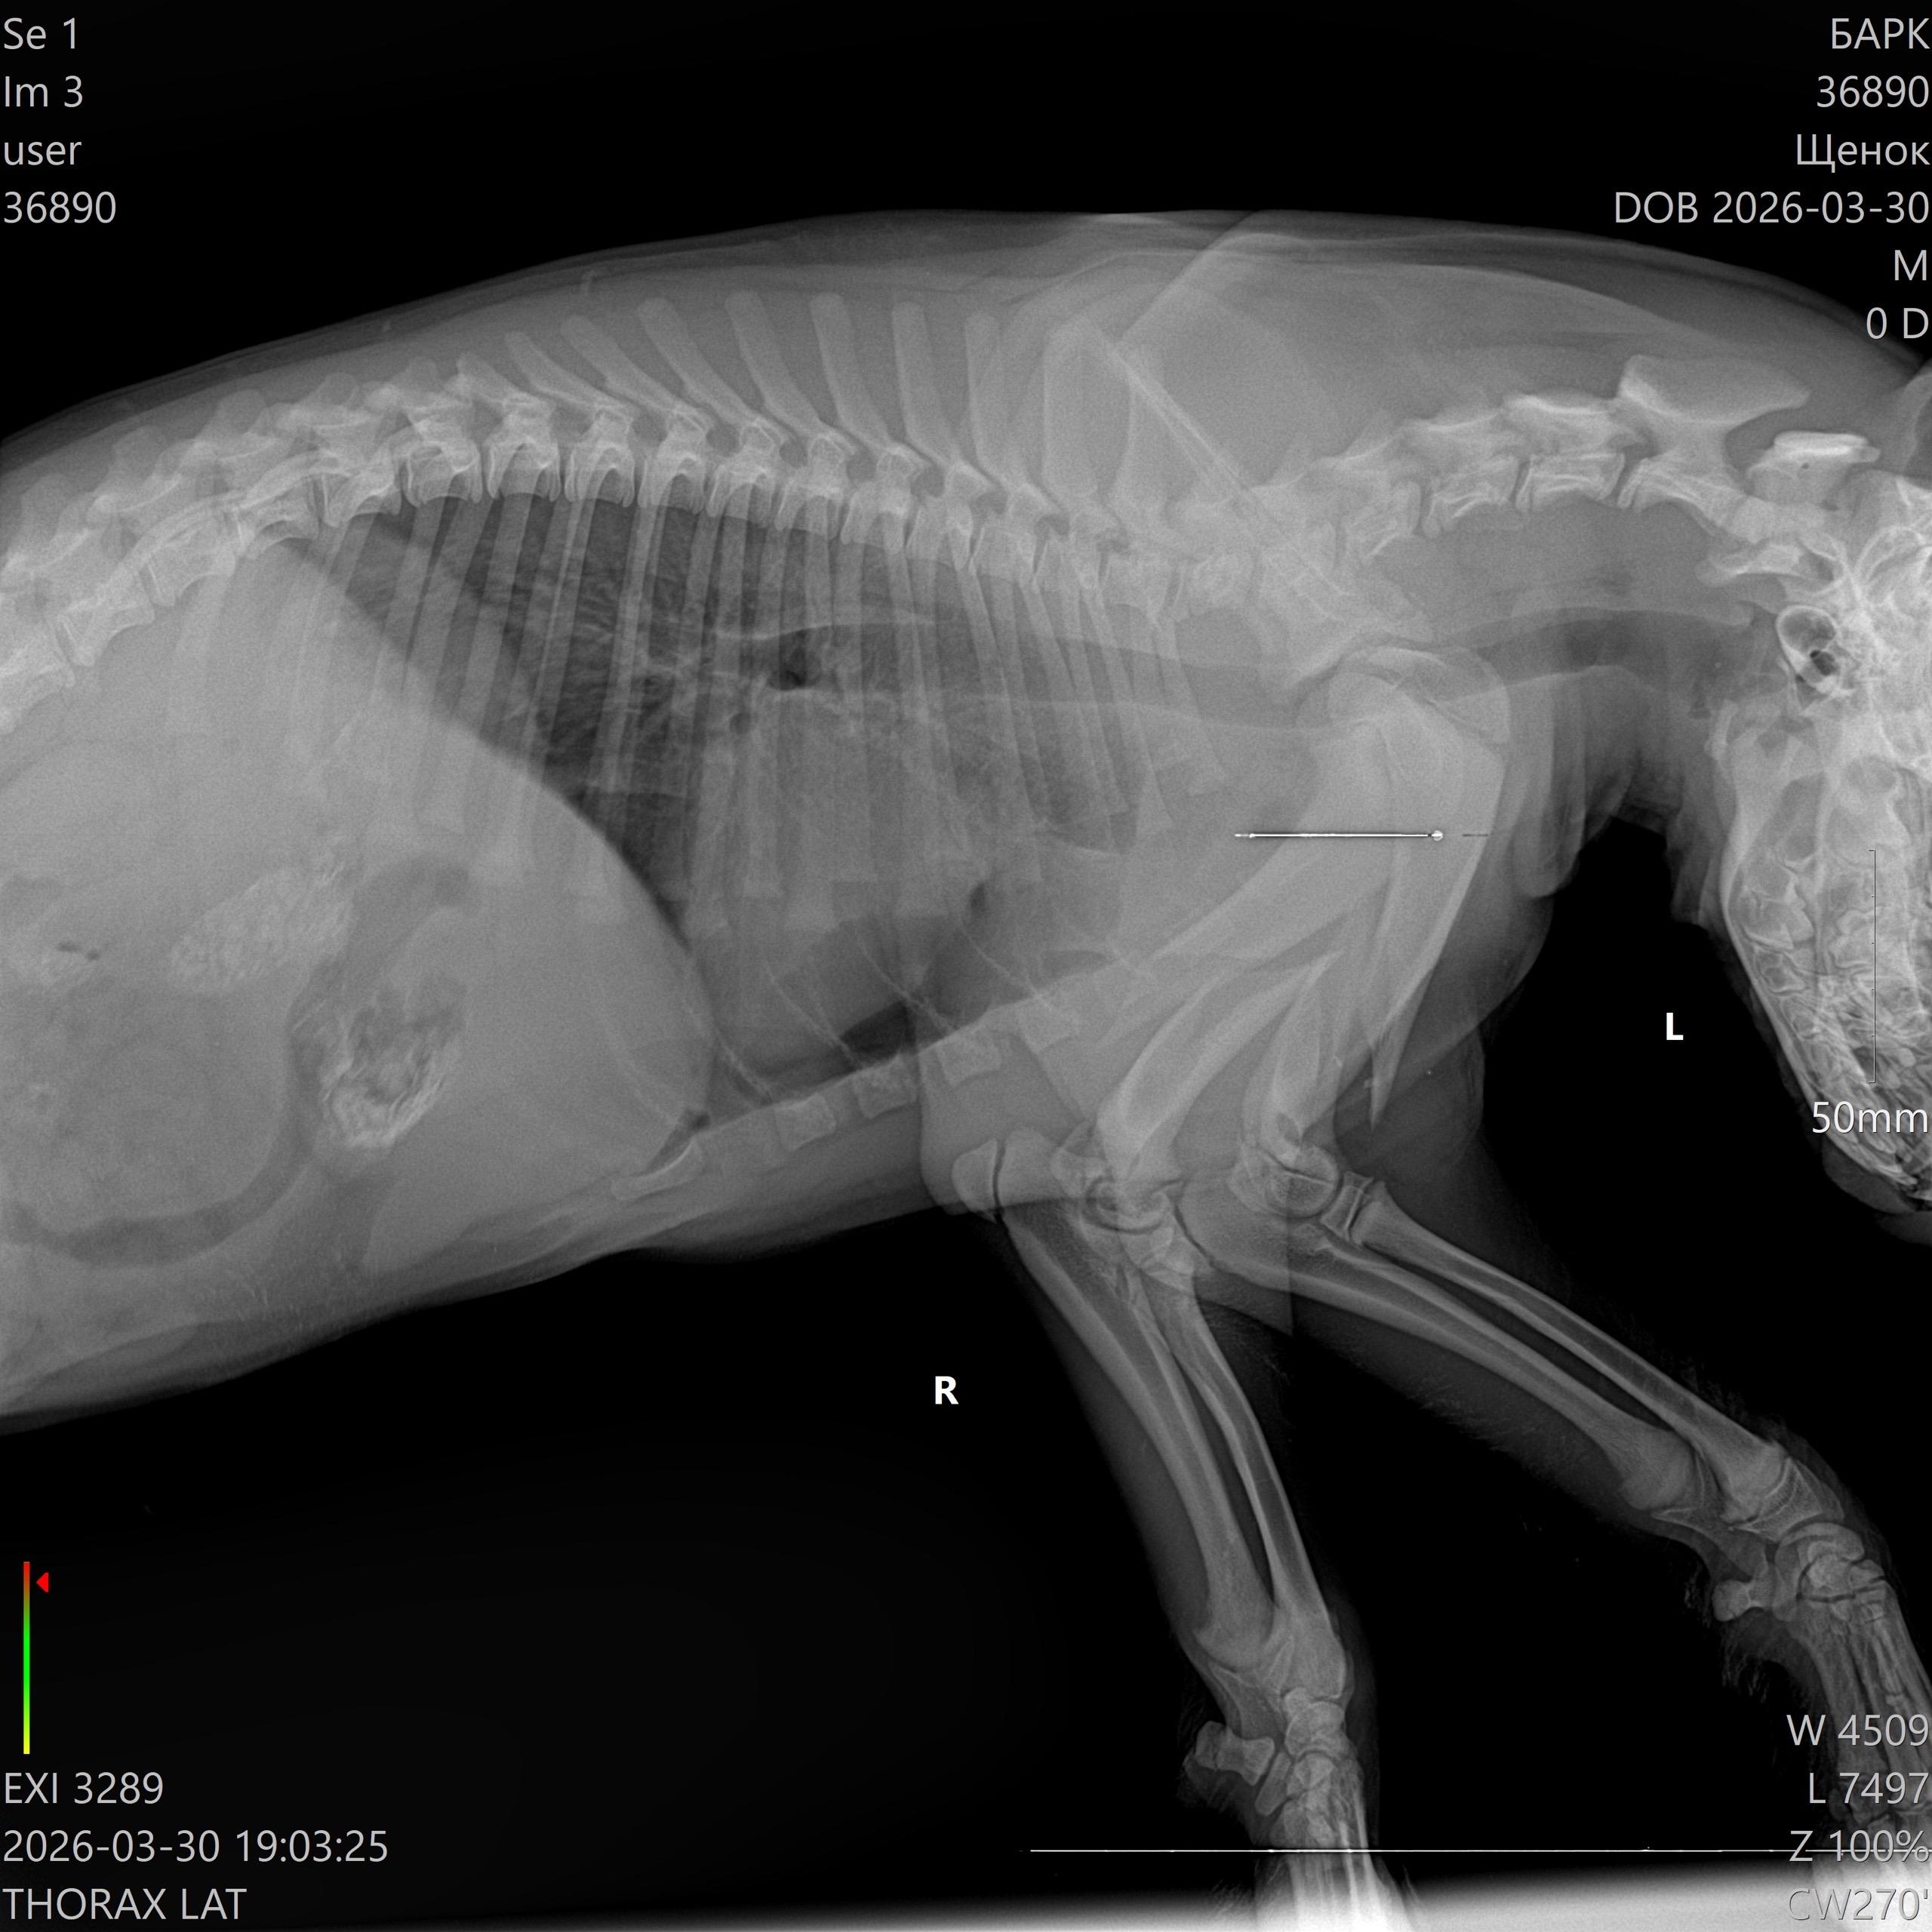

Щенок Булочка после хирургического вмешательства.

31 марта на трассе Архангельск-Новодвинск нашли тяжело травмированного щенка. Его сбили и бросили без помощи. Неравнодушные люди доставили животное в клинику, где диагностировали сложный перелом обеих передних лап.

2 апреля операцию успешно выполнил ветеринарный хирург Александр Чечулин. Щенка, получившего кличку Булочка, теперь восстанавливают. Она уже пытается вставать, но испытывает боль.

Булочке примерно четыре месяца, ее вес составляет 10 килограммов. По прогнозам специалистов, через три месяца у нее есть отличный шанс встать на все лапы и начать бегать.